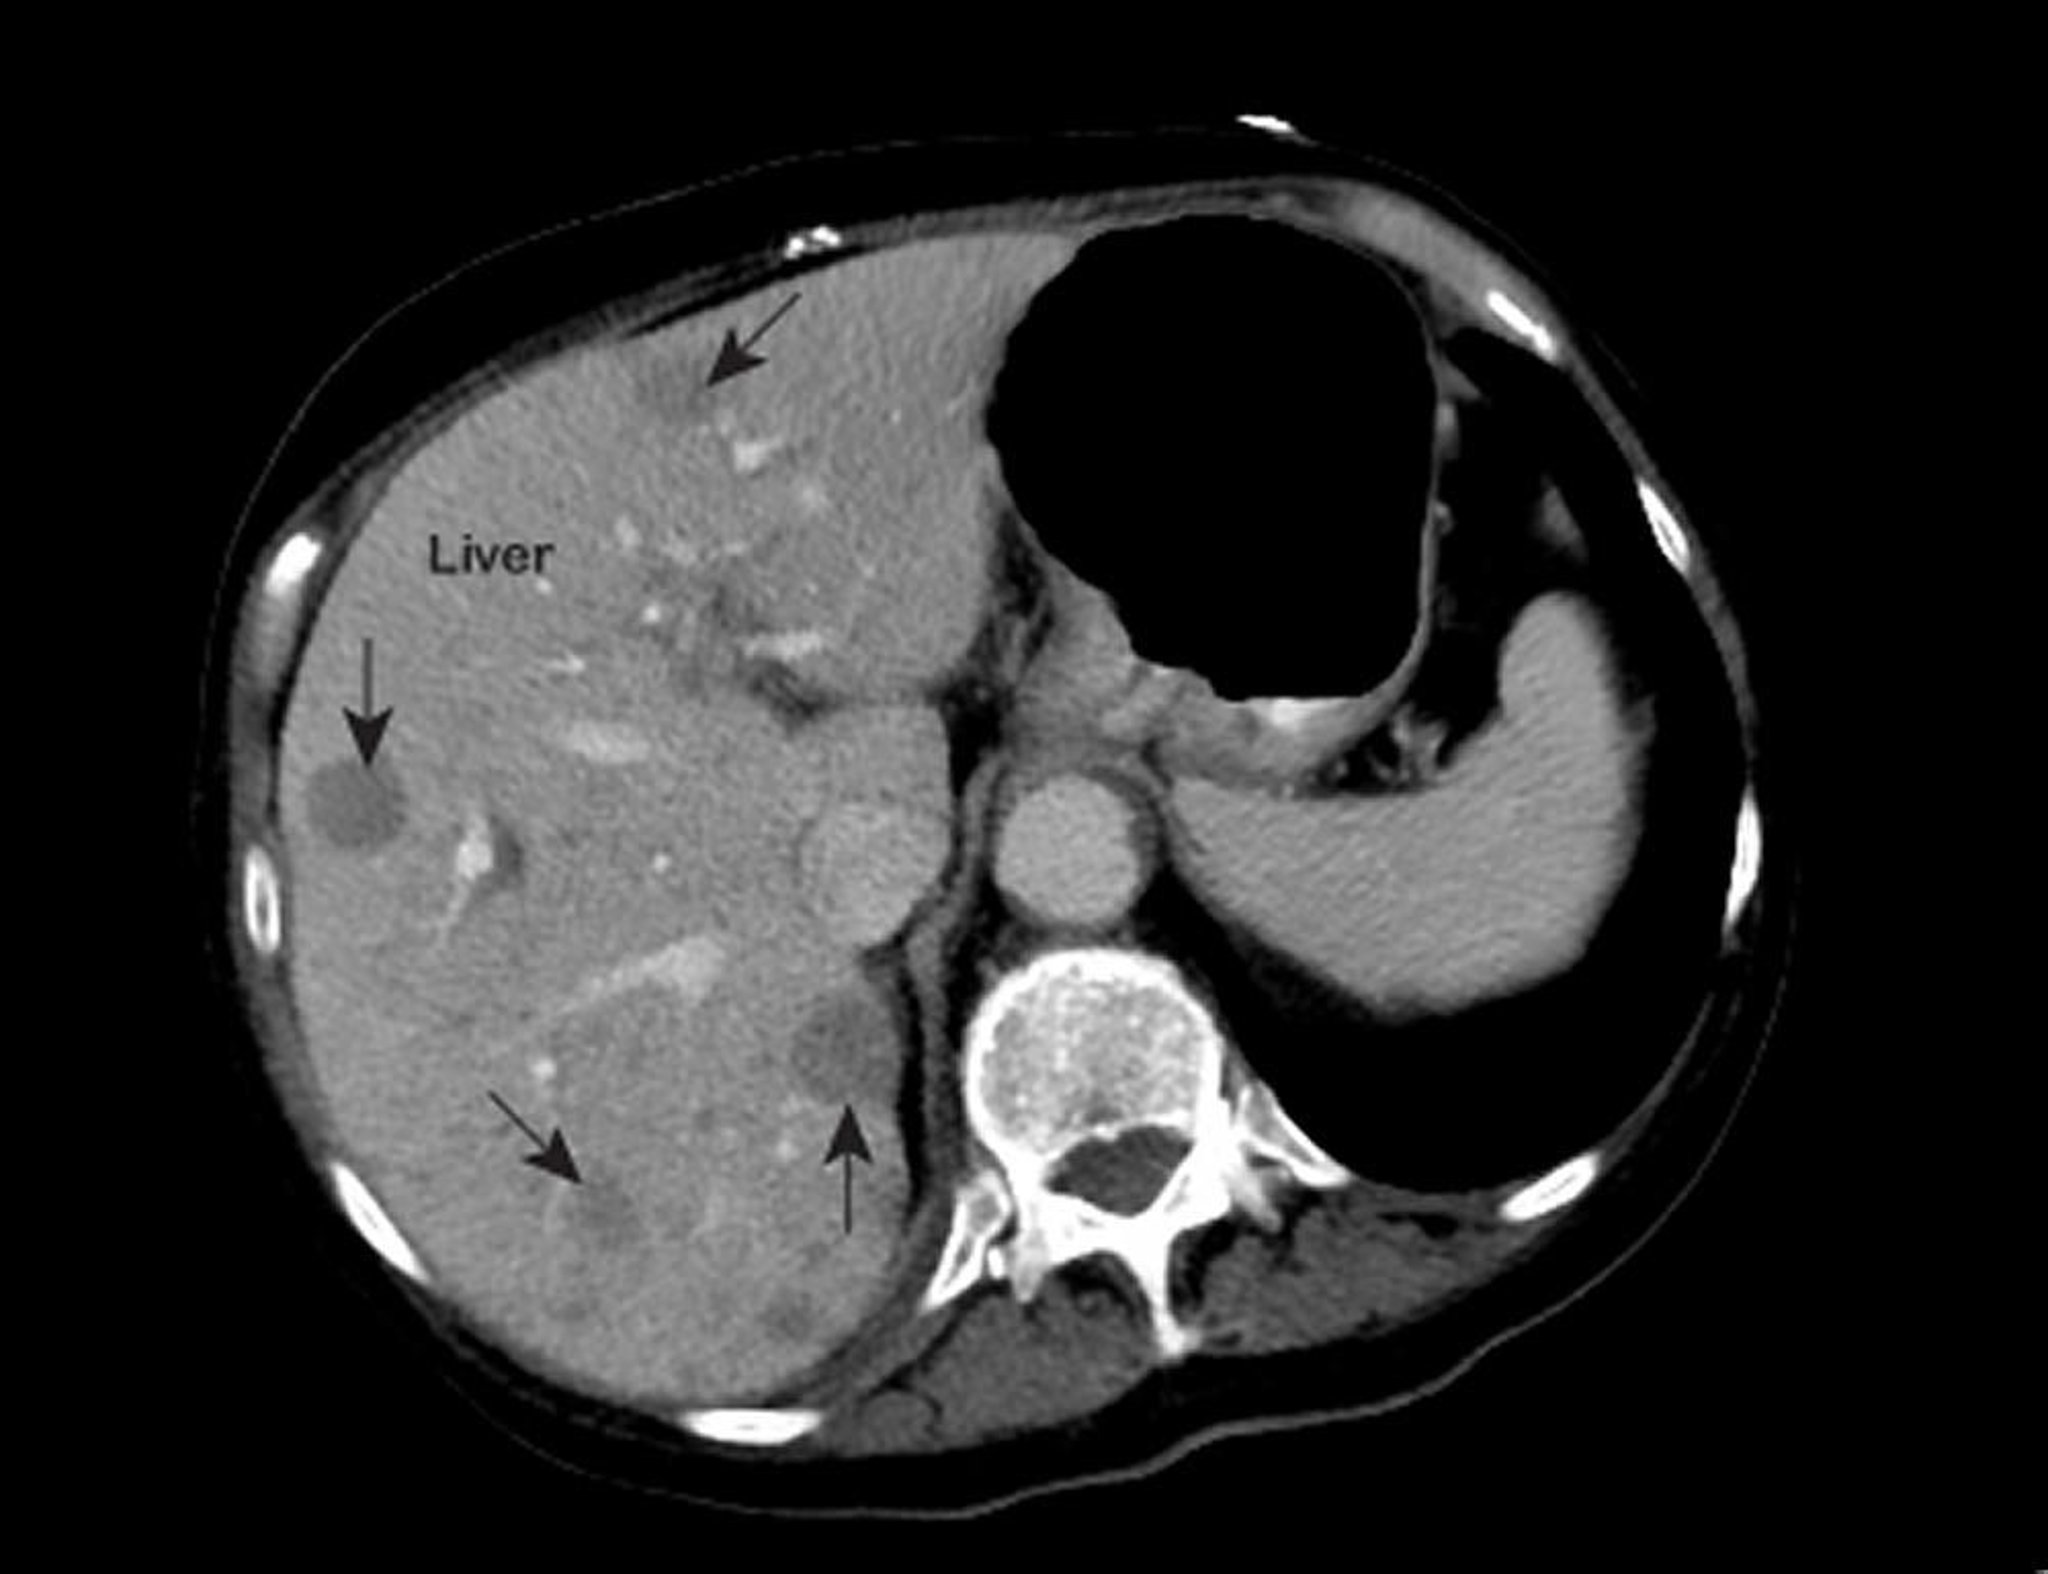

Ung thư gan di căn

Chụp MRI ngực bất thường cho thấy các vùng có độ đậm nhạt thấp (được đánh dấu bằng mũi tên) bên trong gan. Xuất hiện này là dấu hiệu điển hình của ung thư gan di căn.

Ảnh do bác sĩ Patrick O’Kane cung cấp